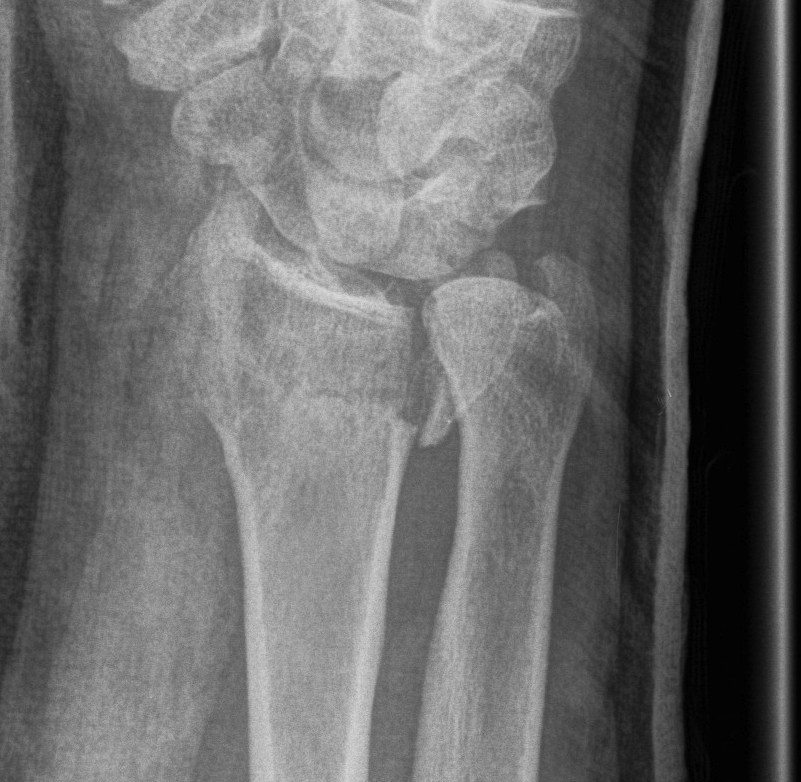

Dr shortDR short

Distal radius fracture with shortening and dorsal tilt

Distal Radius Fracture DRUJ incongruentDRUJ FractureDRUJ Fracture CT

Sigmoid notch disruption and DRUJ instability